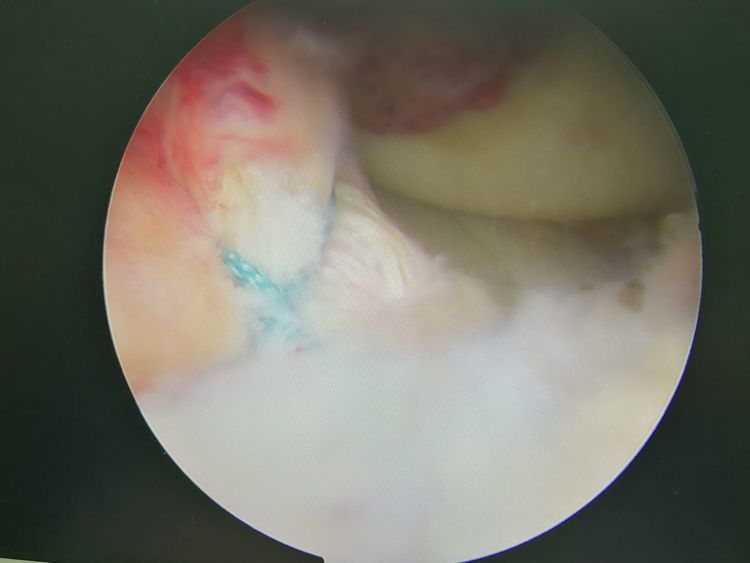

7、 关节镜可施行以往开放性手术难以完成的手术,如半月板部分切除术,肩关节盂唇撕裂修复,踝距骨软骨损伤清理及微骨折手术等。

关节镜适应症:1.用于诊断:①非感染性关节炎的鉴别。从观察到的关节滑膜的充血和水肿、软骨损伤的程度以及关节内有无晶体物等病理改变,可协助区别类风湿性关节炎、骨关节病及晶体性关节炎。②了解膝关节半月板损伤的部位、程度和形态。③膝关节交叉韧带及腘肌腱止点损伤情况。④了解关节内软骨损害情况,有无关节内游离体等,以确诊骨关节病,尤其髌骨软骨软化症。⑤分析慢性滑膜炎的病因,例如色素沉着绒毛结节性滑膜炎。⑥膝关节滑膜皱襞综合征及脂肪垫病变的诊断。⑦肩袖破裂的部位、程度及肱二头肌腱粘连情况。⑧关节滑膜活检。 2.用于研究关节内病变的变化:在关节疾病发展过程中,可多次进行关节镜检查,通过拍照、录像或滑膜活检,可取得其他诊断法所难以得到的资料,对诊断、治疗和预后判断均有极大帮助。 3.用于治疗:对膝、肩关节的一些病变,在明确诊断后,可在镜视下用特殊器械进行手术,而取得满意效果。例如关节灌洗清创术、膝关节撕裂半月板部份或全部切除术、半月板边缘撕裂缝合术、前交叉韧带修复术、滑膜皱襞切除术、关节内粘连松解术、胫骨平台或髁间嵴骨折修整术、肩袖清创术、肱二头肌腱粘连松解术及关节内游离体摘除术等。此外,四肢大关节的类风湿性关节炎可行滑膜大部切除术。

镜下手术图片,展示人体关节镜下情况:

骨科中心近两年共收治关节镜手术病人500余人,本人在近半年共收治关节疾病患者70余人,包括肩关节脱位及盂唇损伤、半月板损伤、交叉韧带损伤、叉韧带止点撕脱、髌骨脱位、色素性滑膜炎、关节游离体、老年骨性关节炎、踝关节外侧副韧带损伤伴距骨软骨损伤等。均通过关节镜或辅助关节镜手术治疗,短期内随访效果好,总体满意率在95%以上。